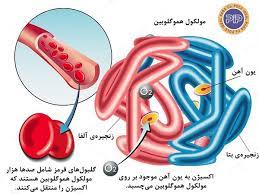

قیمت: 32٬000 تومان - دسته بندی فایل: علوم پزشکیپاورپوینت برنامه های ملی مبارزه با بیماری های غیر واگیر تالاسمی

فروش ویژه پاورپوینت حرفه ای برنامه های ملی مبارزه با بیماری های غیر واگیر تالاسمی با تخفیف استثنایی فقط 62 هزار تومان تعداد اسلاید: 24 اسلاید